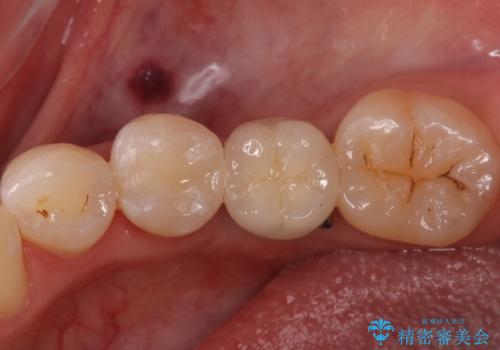

セラミックインレーでの治療を行いました。

- 左下5 セラミックインレー 77,000円費用は治療当時の料金となります

銀の詰め物のやり替えは2回の来院で終わらせることができます。

下の歯は口を開けたときに外からよく見えるため、セラミックにやり替えることで印象が大きく変わります。